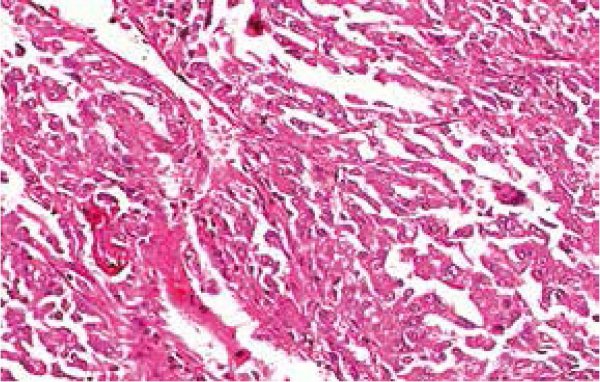

Al examen microscópico muestra una masa tumoral con 80% de material necrótico,y20% muestraunaproliferación tumoral de tipo sarcomatoide, con núcleos discarioticos, pleomorficos; en sectores se observa láminas de células epiteliales de abundante citoplasma claro, núcleos irregulares, de cromatina fina; tejido conectivo con moderado infiltrado inflamatorio linfoplasmocitario; esta formación tumoral se encuentra separada de la fascia de Gerota, no se observa células neoplásicas, sin embargo se identifican permeaciones linfovasculares (FIGURA 4).

FIGURA 4: Microfotografía 400x: Se observa a mayor detalle la presencia de células tumorales con cambios anaplasicos de los núcleos.